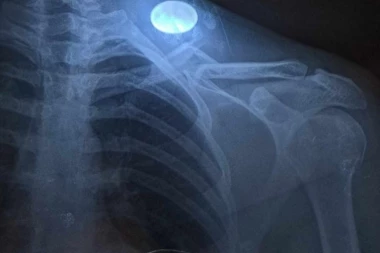

Fudbal niže lige 15:19 19.03.2024 UŽAS: Utakmica je ostala u senci teške povrede fudbalera - šestostruki PRELOM ključne kosti!